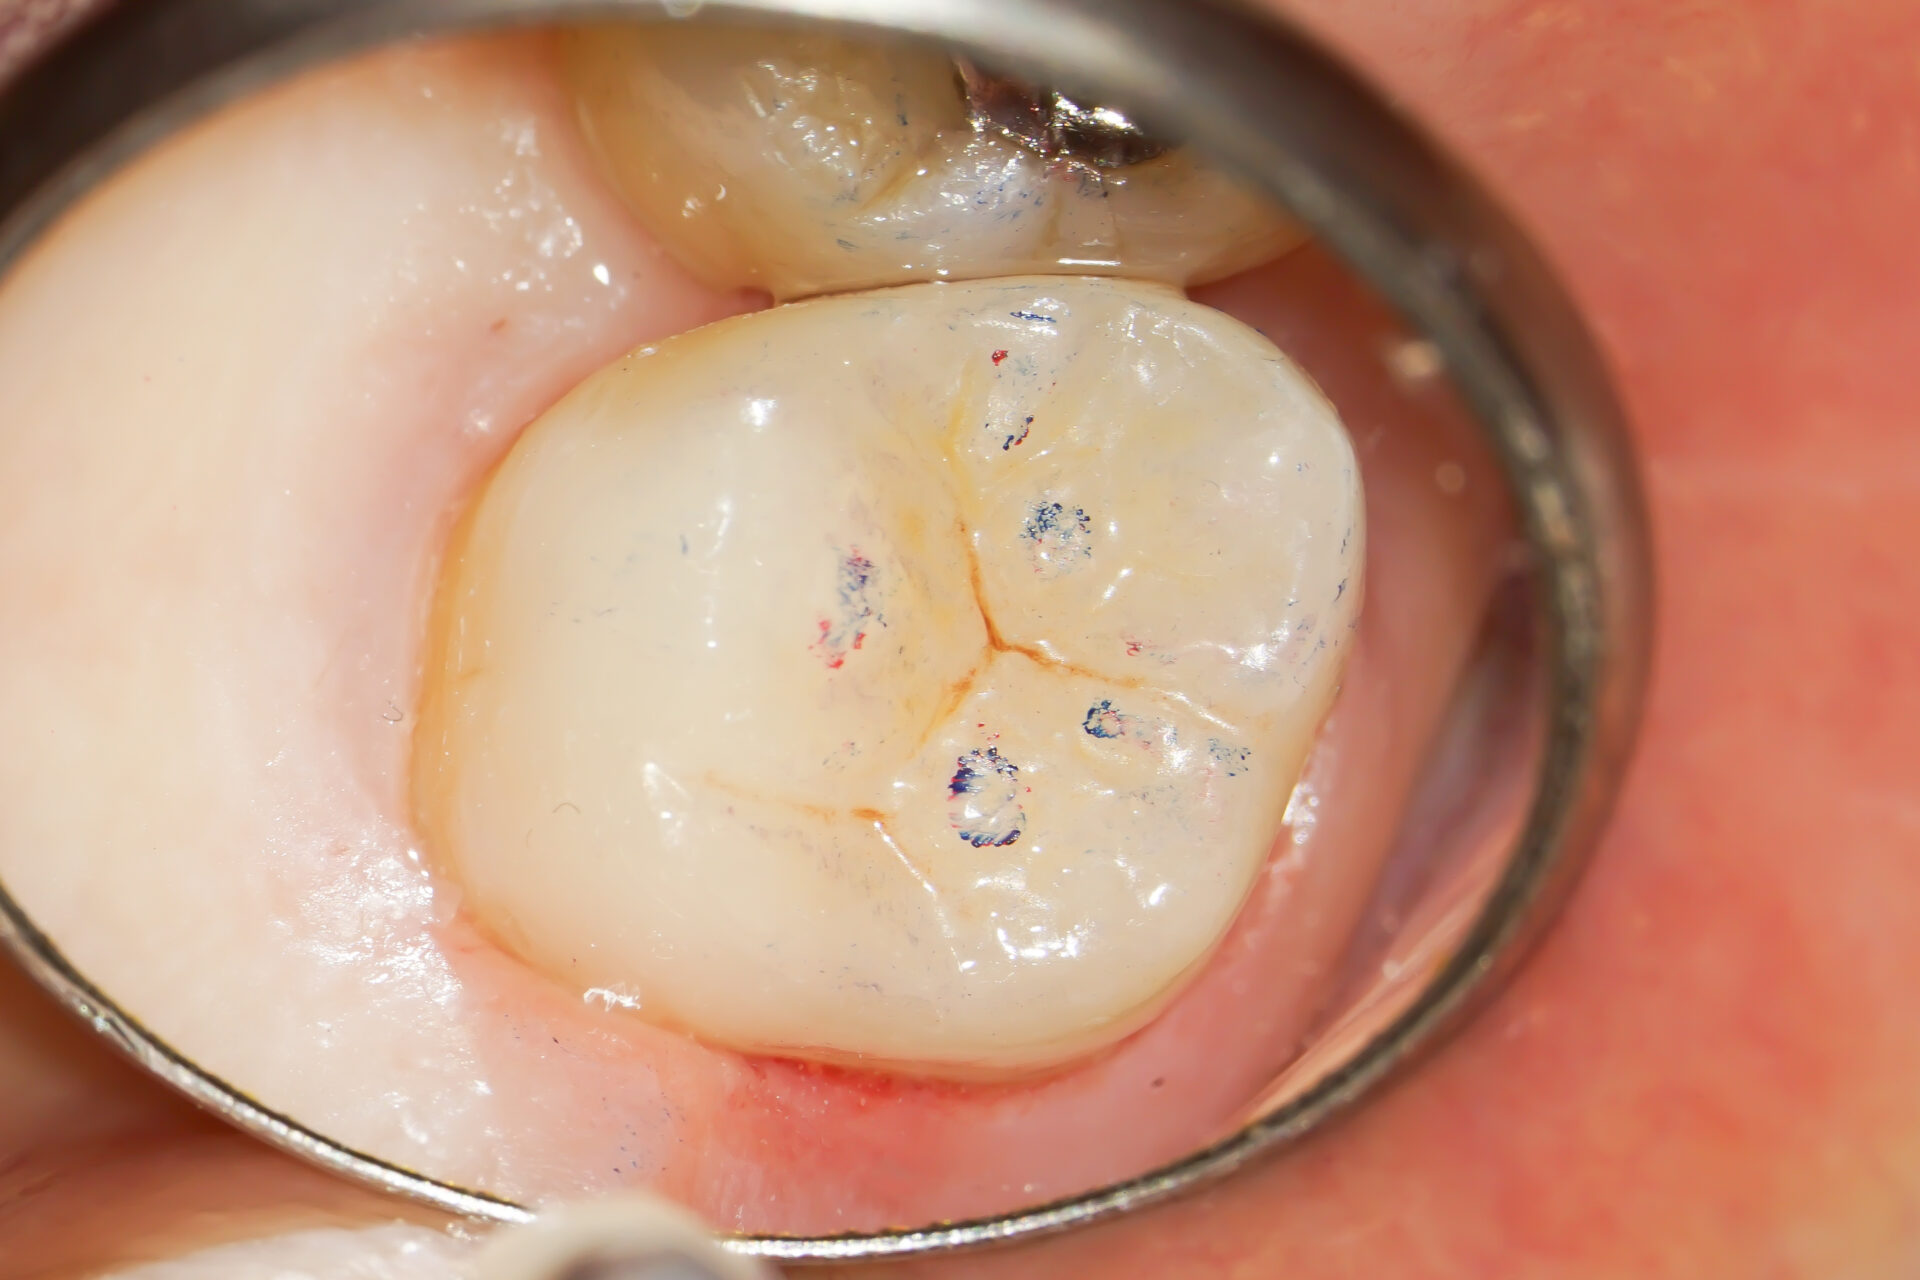

後日、セラミックが出来上がってきたのでセットしていきます。

コンポジットレジンにて時間をかけ、精密に接着を行います。

接着後は研磨してセラミックとの境目が見えないように仕上げていきます。

咬合状態もばっちりです。